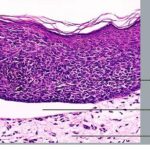

Superficial Basal Cell Carcinoma

Superficial BCC is characterized microscopically by buds of malignant cells extending into the dermis from the basal layer of the epidermis. The peripheral cell layer shows palisading. There may be epidermal atrophy, and dermal invasion is usually minimal. This histologic sub-type is encountered most often on the trunk and extremities but may also appear on the head and neck. There may be a chronic inflammatory infiltrate in the upper dermis.